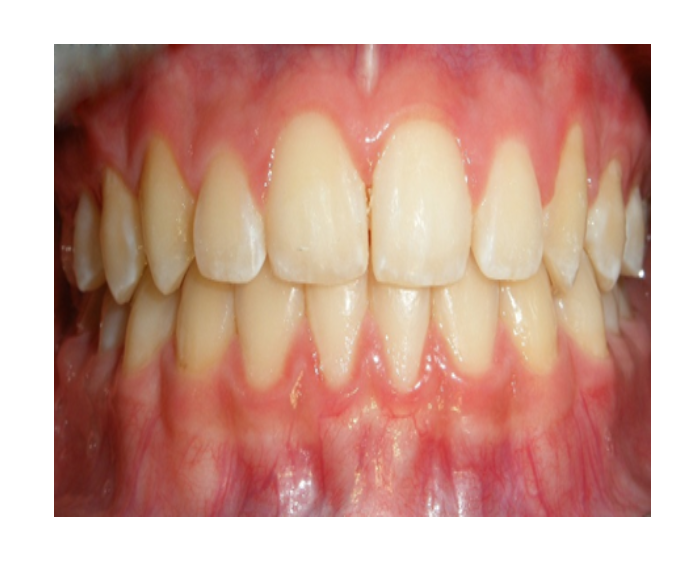

Mordida Cruzada posterior unilateral